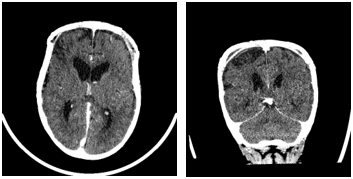

Day 1 postoperatively she developed left-sided focal seizures (left arm jerking, left facial twitching) 8 seizures were recorded in total lasting approximately between 30s-35mins. The first seizure initially responded to buccal Midazolam, but the seizures were fully abated by Phenytoin and Phenobarbitone. On examination following the seizures, she was noted to have left-sided weakness (left hemiparesis). A subsequent CT Brain revealed acute right frontal and medial right parietal infarcts (Figures 2A & 2B). An MRI brain showed extensive bilateral areas of acute infarct distribution suggestive of watershed infarcts worse on the right side and absence of signal flow within the supraclinoid segment of both internal carotid arteries (ICA). CTA showed absence of flow with the supraclinoid segments of both ICA, in keeping with occlusion and evolution of bilateral infarcts right greater than left (Figure 2C). She was then commenced on Aspirin. IR with general anaesthesia (GA) revealed bilateral supraclinoid ICA occlusion, consistent with moyamoya syndrome (bilateral occlusive cerebrovascular disease) (Figures 3A & 3B). Following the review of imaging by a multidisciplinary team, it was agreed that she was not fit for any pial synangiosis surgery or burr hole surgery in relation to the moyamoya disease as she was at very high risk of further strokes and surgery should be avoided wherever possible as the risk of general anaesthesia would also be considerable for her.

Figure 3: A & B) IR Angio shows: revealed bilateral supraclinoid ICA occlusion, consistent with moyamoya syndrome.